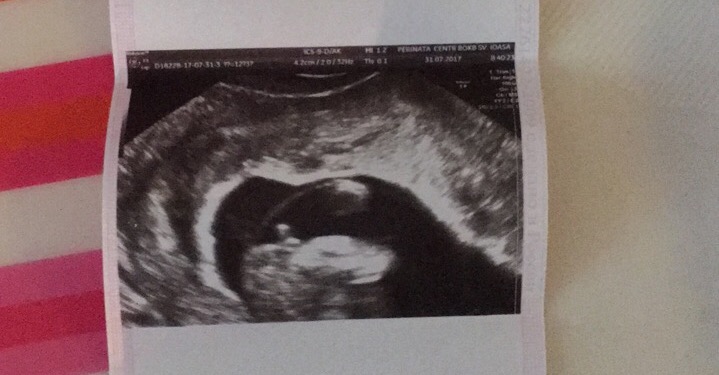

Пол малышаДевочки покидайте у кого есть фотки узи в 14-15 недель того самого места ))).на первом скрине сказали с большой вероятность парень .Сегодня в 14,3 уже другая врач сказала точно девочка ,фотку дала,но я уже чёт сомневаюсь первое фото 14,3;второе 12,6

Девочка это

У моего мальчика между ног в 16 недель было вот так,тоже прям пениса не видно,но врач сразу и четко сказала,что мальчик.Иначе чем на вашем узи.

Смешно, ей богу. В 20 недель узнаете точно. До 16 недель пол ребенка - все равно что погадать на кофейной гуще. У всех одинаковый половой бугорок, половые органы ещё не сформированы. Есть специалисты которые могут предположить пол с большей или меньшей вероятностью по углу наклона полового бугорка, но смотрят и померить можно когда малыш лежит сбоку и уж никак не со стороны попки:) наберитесь терпения. Мальчик там или девочка главное малыш здоров:)

Я думала ,да и в пред моей посте писали что к 14 неделям пол сформируется .на первом скрине понятно что гадают по наклону бугорка .А вот в 15 я думала уже видно будет ,ещё и узистка сказала точно без вариантов девочка .